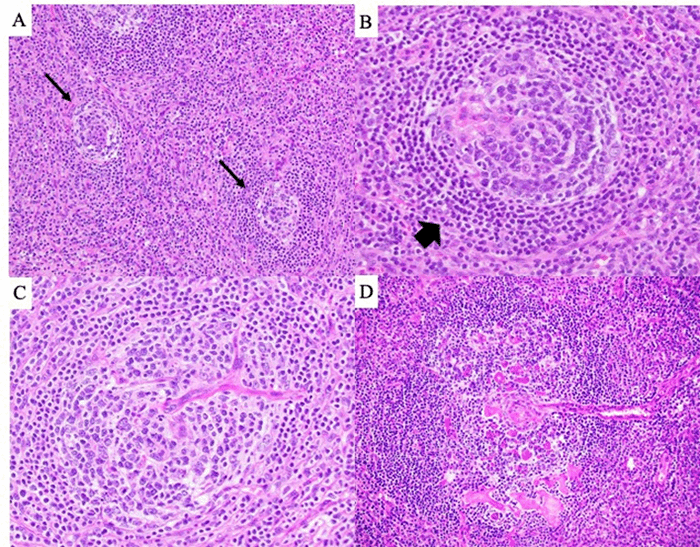

Final pathology revealed an 8.8 × 7.8 × 5.9 cm mass (Figure 1B) characterized by regressively transformed, atretic follicles, “onion-skinning” of mantle zones, and hypervascularity, including vessels penetrating follicles at right angles (Figure 2). Extrafollicular areas exhibited fibrosis, SMA-positive spindled cells, increased plasma cells, myxoid change, and focal necrosis (Figure 3A). ALK1 staining was positive in the spindled areas and a subset of non-lymphoid follicular cells (Figure 3B and C). Fluorescence in situ hybridization (FISH) analysis confirmed an ALK rearrangement (Figure 3D).

Figure 2. Histopathologic Features. Published with Permission

(A) Atretic follicles (arrows), 100x magnification. (B) "Onion skinning" of the mantle zone (arrow), 200x magnification. (C and D) Vessels penetrating follicles at right angles, 200x magnification.